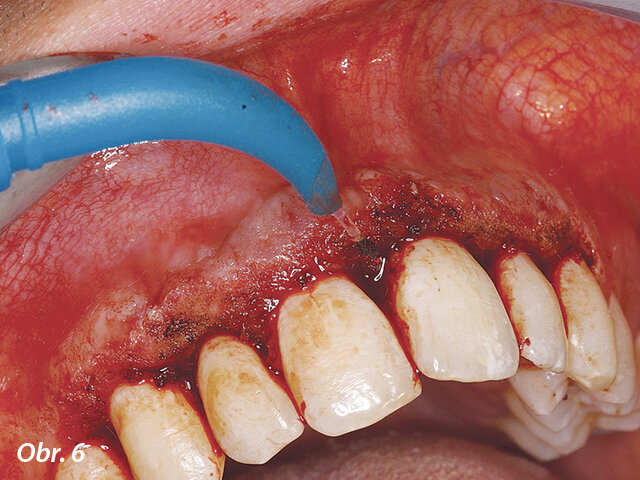

V druhé kazuistice se jednalo o dospívajícího pacienta s hyperplastickou gingivitidou v horním frontálním úseku.

Odstraňování nežádoucích hyperplastických tkání pomocí diodového laseru AMD Picasso s jednorázovým hrotem.

Po odstranění hyperplastických tkání v horním frontálním úseku byl patrný posun směrem k požadovaným výsledkům.